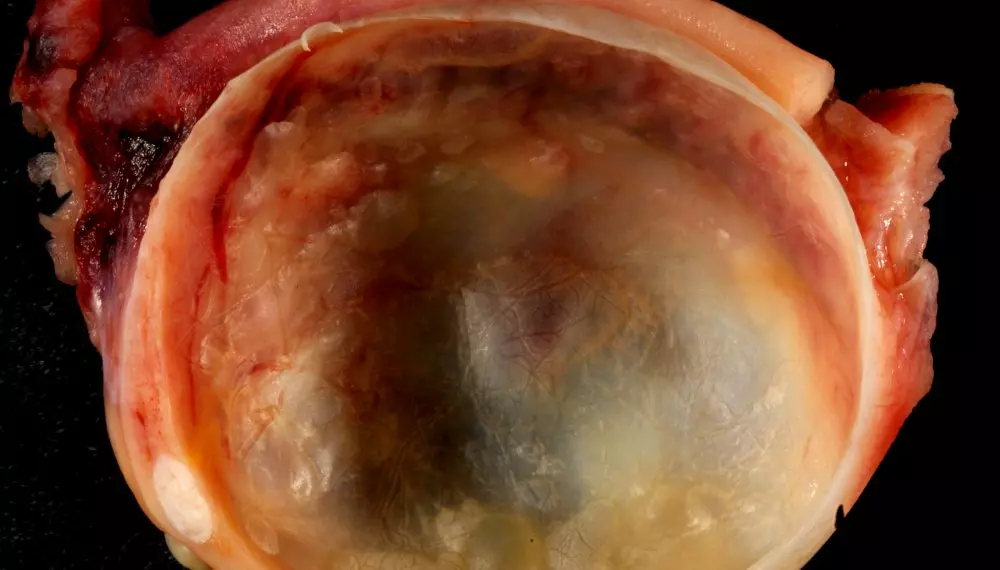

There Was A Big Cyst Growing Inside Katie

The Type Of Cyst Was Going To Be Important

The doctors started examining the cyst. What they were looking for was the type of cyst. They had to make sure that the cyst was not dangerous. If the cyst was solid then it would have been dangerous. However if the cyst was soft or liquid then it could be controlled. Solid cysts can be very dangerous and they are more likely to be cancerous. Katie was very concerned now as she wanted to know as quickly as possible about what the cyst is going to be like. Now was the time to move forward with more tests.

After the X-ray showed that there was a cyst inside Katie’s body. The doctors ordered more tests. Tests were done to see if there were other complications due to the cyst. After the tests Katie took a sigh of relief as the cyst was liquid. It was very important to know the nature of the cyst and once the doctors found out that the cyst was liquid they knew that they could put Katie on path to recovery. Liquid cysts are relatively easier to treat as compared to solid cysts. So it was a sort of a good news for Katie.

The Big Size Of The Cyst Was Dangerous For Katie

The size of cyst is also very important. When cysts start to grow bigger then they usually become more dangerous and are more prone to infection. The larger cysts are also more difficult to remove and usually require a long surgery to remove them from the body. Unfortunately for Katie, the cyst in her body had become really big and she knew that there was no other option but to get a surgery done for the removal of the cyst. These surgeries can be very dangerous for the patient depending on the size and nature of the cyst.

The Cyst Was On Her Ovaries

The position of the cyst is also very important. The part where the cyst grows or is attached to the human body can actually have a great effect on your body and the risk factor of the surgery. These cysts can grow in tissues and in other parts of the body and can be very dangerous and painful. In Katie’s case, the cyst was on her ovaries. This was a dangerous area for the cyst and it made the surgery more risky. Now the doctors knew that they had to be extra careful during the surgery to make it successful.

The Cyst Was Putting Pressure On Other Organs

There Was One Good News: The Cyst Wasn’t Cancerous

Katie’s Cyst Was The Biggest

Where Kayla and Keely both had cysts that were around 50 pounds, the case was different for Katie. Not only was Katie younger than the two other women, her cyst was also larger than the cyst found in Keely or Kayla. The cyst found inside Katie was actually around a 100 pounds which is almost double the size found in the other two girls individually. If you measure that in terms of a person that is equal to a 13 year old boy. Once Katie, heard about the size of the cyst she just wanted to get rid of it as soon as possible.